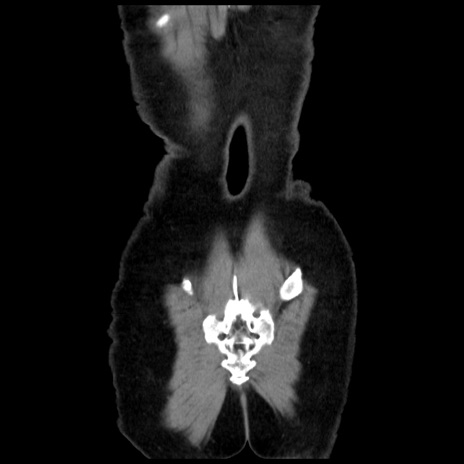

横断像